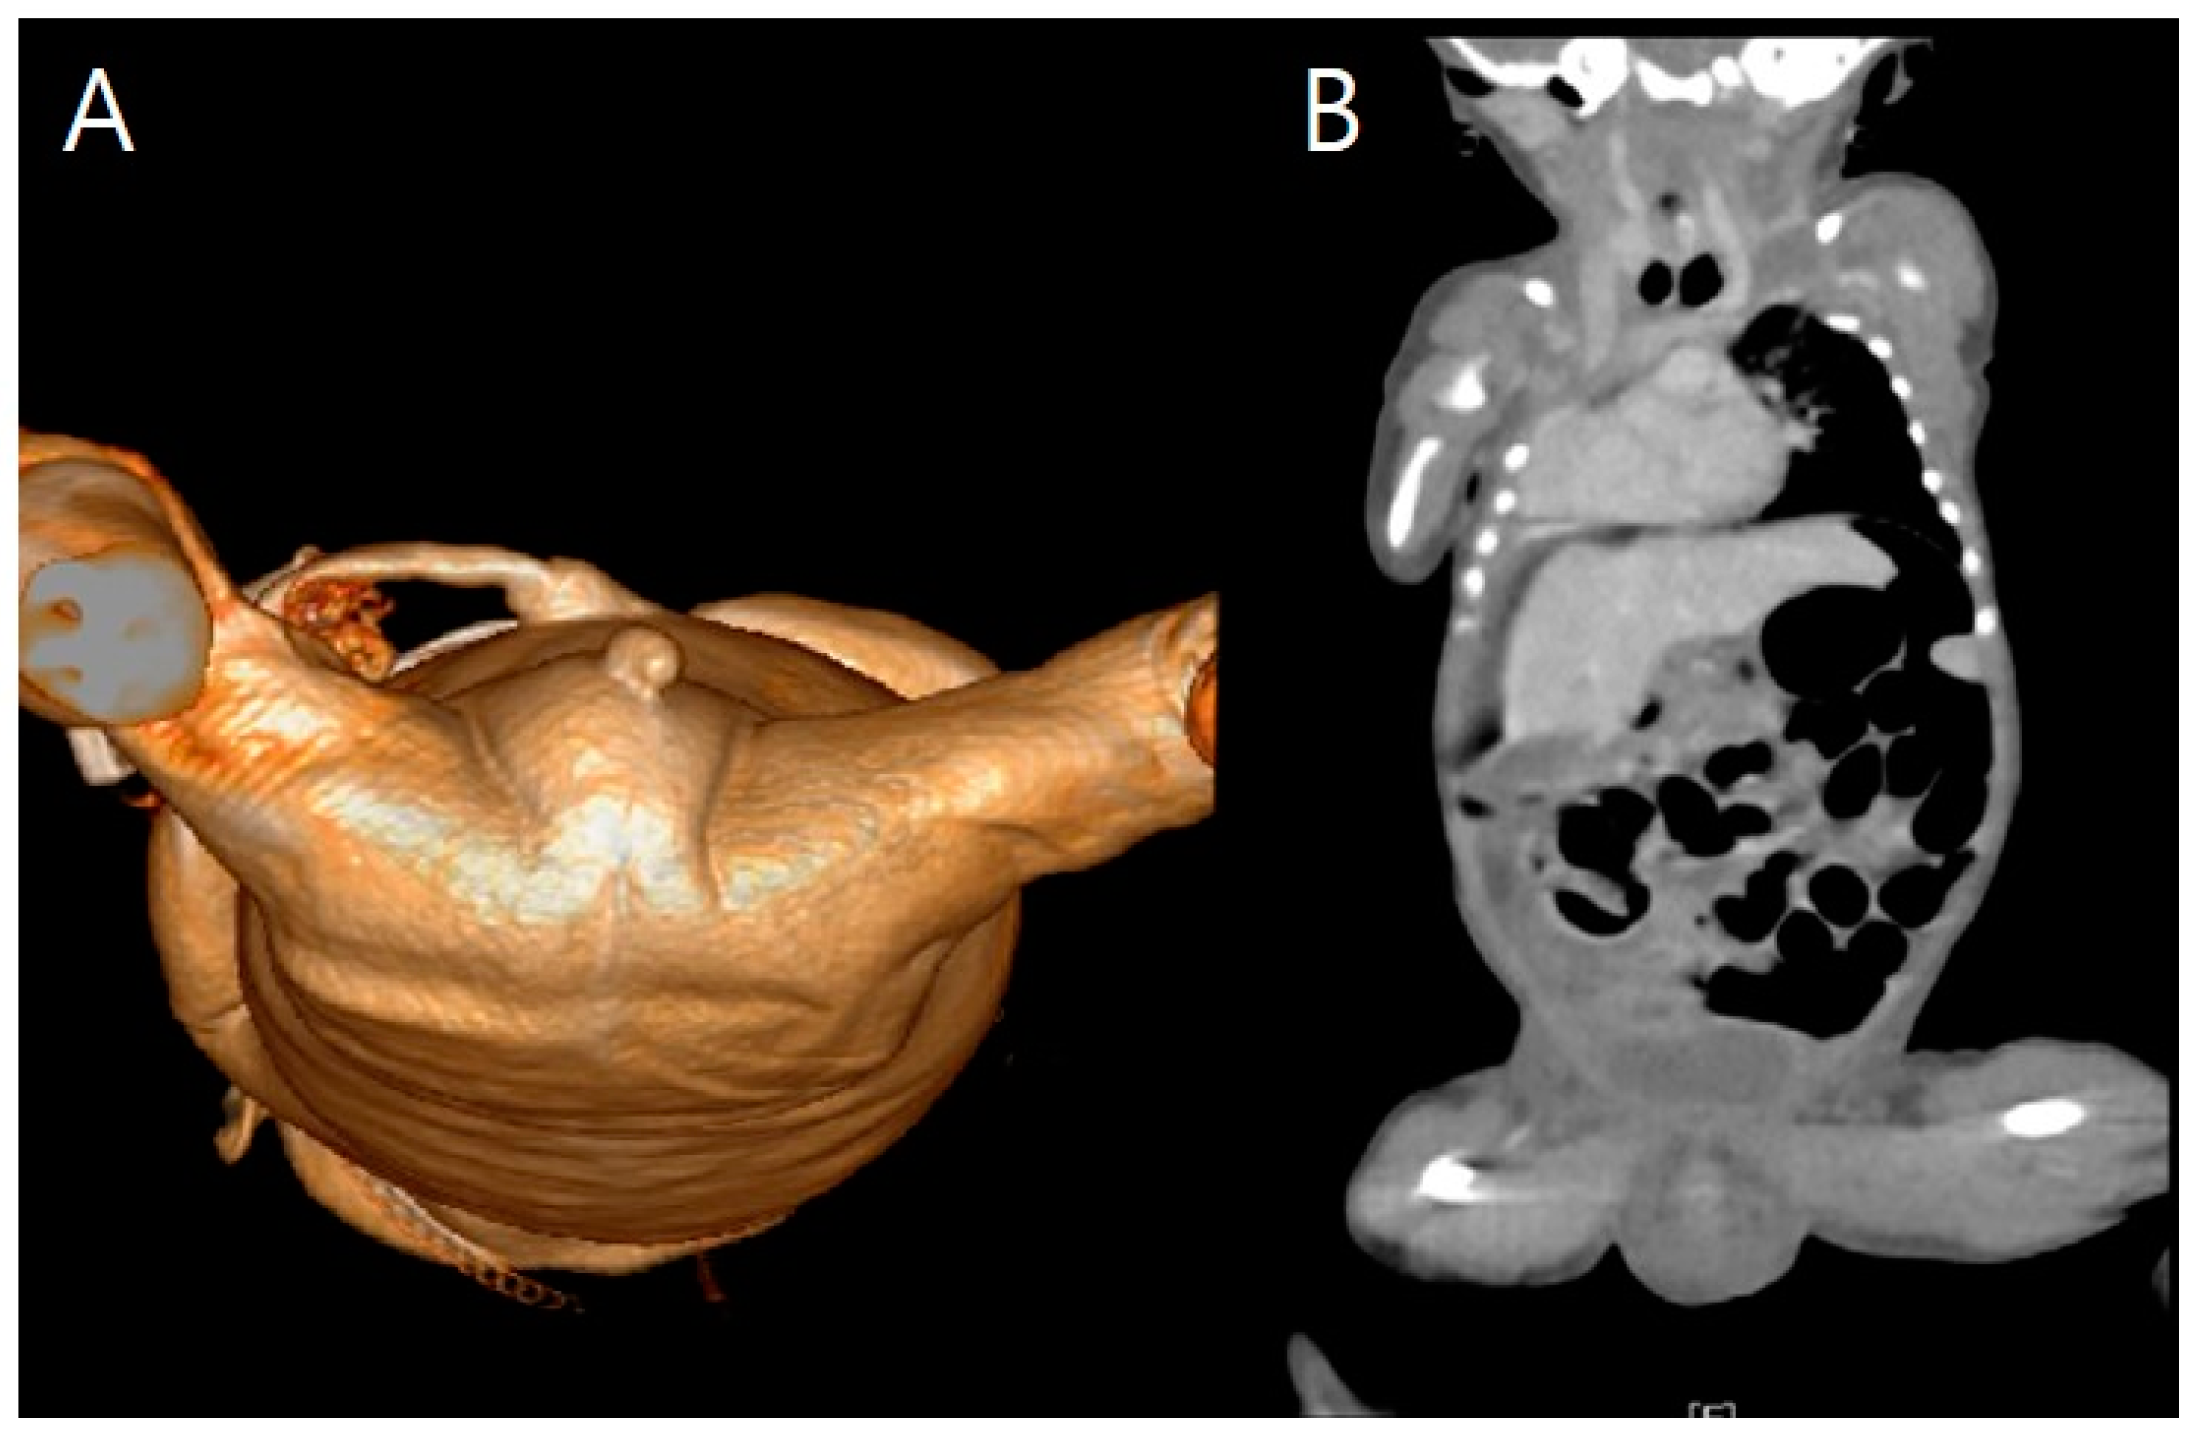

Figure 8. 3D cardiac angio computed tomography of fetus A. (A) Dextrocardia of embryonic arrest with pulmonary hypoplasia from posterior to anterior coronal view. (B) Dextrocardia of embryonic arrest with pulmonary hypoplasia from anterior to posterior coronal view. (C) Tracheoesophageal fistula with right bronchus (white arrow). (D) Tracheoesophageal fistula with right bronchus (yellow arrow).

On the transverse view, we noted a small stomach in association with polyhydramnios in fetus A. These were crucial findings from the prenatal ultrasound examinations for the diagnosis of tracheoesophageal fistula (TEF), which were confirmed by 3D CT (Figure 6 and Figure 8). Compared with the normal-sized stomach filled with amniotic fluid in fetus B, fetus A’s stomach size did not increase over time, as shown by repeated exams (Figure 6).

At 34 + 0 weeks gestation, an emergency cesarean delivery was performed because of relapsed preterm labor. The first baby was a male with VACTERL-H association, weighing 1390 g, and the second baby was a healthy female, weighing 1890 g. The Apgar scores at 1 and 5 min were 6 and 8 in the first twin baby and 5 and 8 in the second twin baby. The first twin had multiple anomalies diagnosed prenatally. Related imaging studies were performed, including an infantogram and 3D CT (Figure 8, Figure 9, Figure 10, Figure 11 and Figure 12). A cardiacangio 3D CT revealed dextrocardia of embryonic arrest with pulmonary hypoplasia and a tracheoesophageal fistula with a right bronchus (Figure 8). The infantogram and 3D CT showed upper-limb agenesis, which aligned with the prenatal diagnosis, including aplasia of the right proximal humerus, radial hypoplasia, and hypoplastic thumb (Figure 9, Figure 10 and Figure 11). The first twin baby also had an imperforate anus and colon dilatation (Figure 12). Neonatal echocardiography showed dextrocardia with right atrial enlargement and an interrupted inferior vena cava without major congenital cardiac abnormalities. The findings from postnatal imaging supported the prenatal diagnosis of a VACTERL-H association. On his fifth day of life, the twin baby with the VACTERL-H association died.